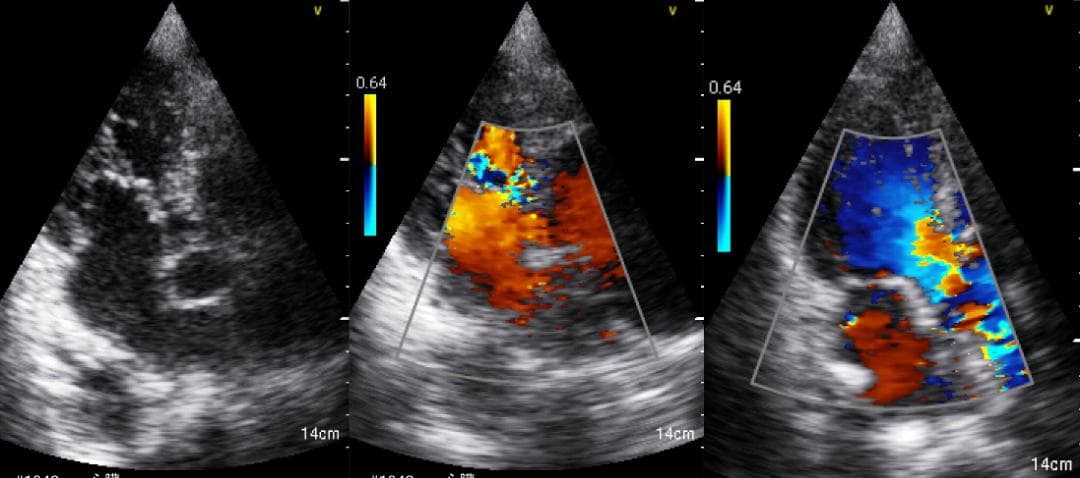

おわかりになる方のみの購入をお願いいたします実際に実施した写真をあげました正常肝臓、胆石症、頸動脈プラーク、同じく頸動脈プラーク、Mrの収縮期、同じくM弁の開放期とA弁の開放期、腹部大動脈瘤、正常の頸動脈、甲状腺右葉の結節、前立腺肥大画像の描出は条件によりますがご検討をお願いいたします経年変化、使用に伴うスレや傷などがあります機能に問題はありませんスキャンは心血管、腹部、体表に対応します外部接続端子のカバーが一部壊れていますが蓋は閉まりますバッテリーはフル充電されますが劣化はあると思います医療用モニタリング機器 Vscan Extend、GE- モデル名: Vscan Extend- ブランド: GE- 色: ホワイト- 機能: 医療用モニタリング機器ご覧いただきありがとうございます。セブンプレミアム 耳が痛くなりにくい やわらかマスク385枚。